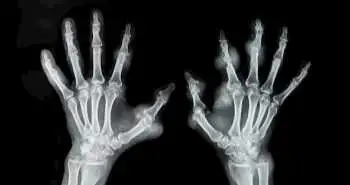

The results of a systematic review and meta-analysis of randomized controlled trials (RCTs) including rituximab combined with methotrexate (MTX) and MTX only indicate that the combination therapy offered significantly higher ACR20, ACR50, and ACR70 in rheumatoid arthritis patients as compared to the MTX alone. There was no difference between total complication and infection rates. An electronic search of PubMed, Google database, the Cochrane Library, and the Chinese Wanfang database was carried out to extract RCTs for the meta-analysis.

The study outcomes were improvement in ACR20, ACR50, ACR70, total complications and infection rate. In the selected 5 RCTs, 3299 patients were in the rituximab-MTX group and 1512 were in MTX only group. This meta-analysis showed that the combination therapy was effective and safe for RA patients, long-term safety evaluation yet to be done in future.